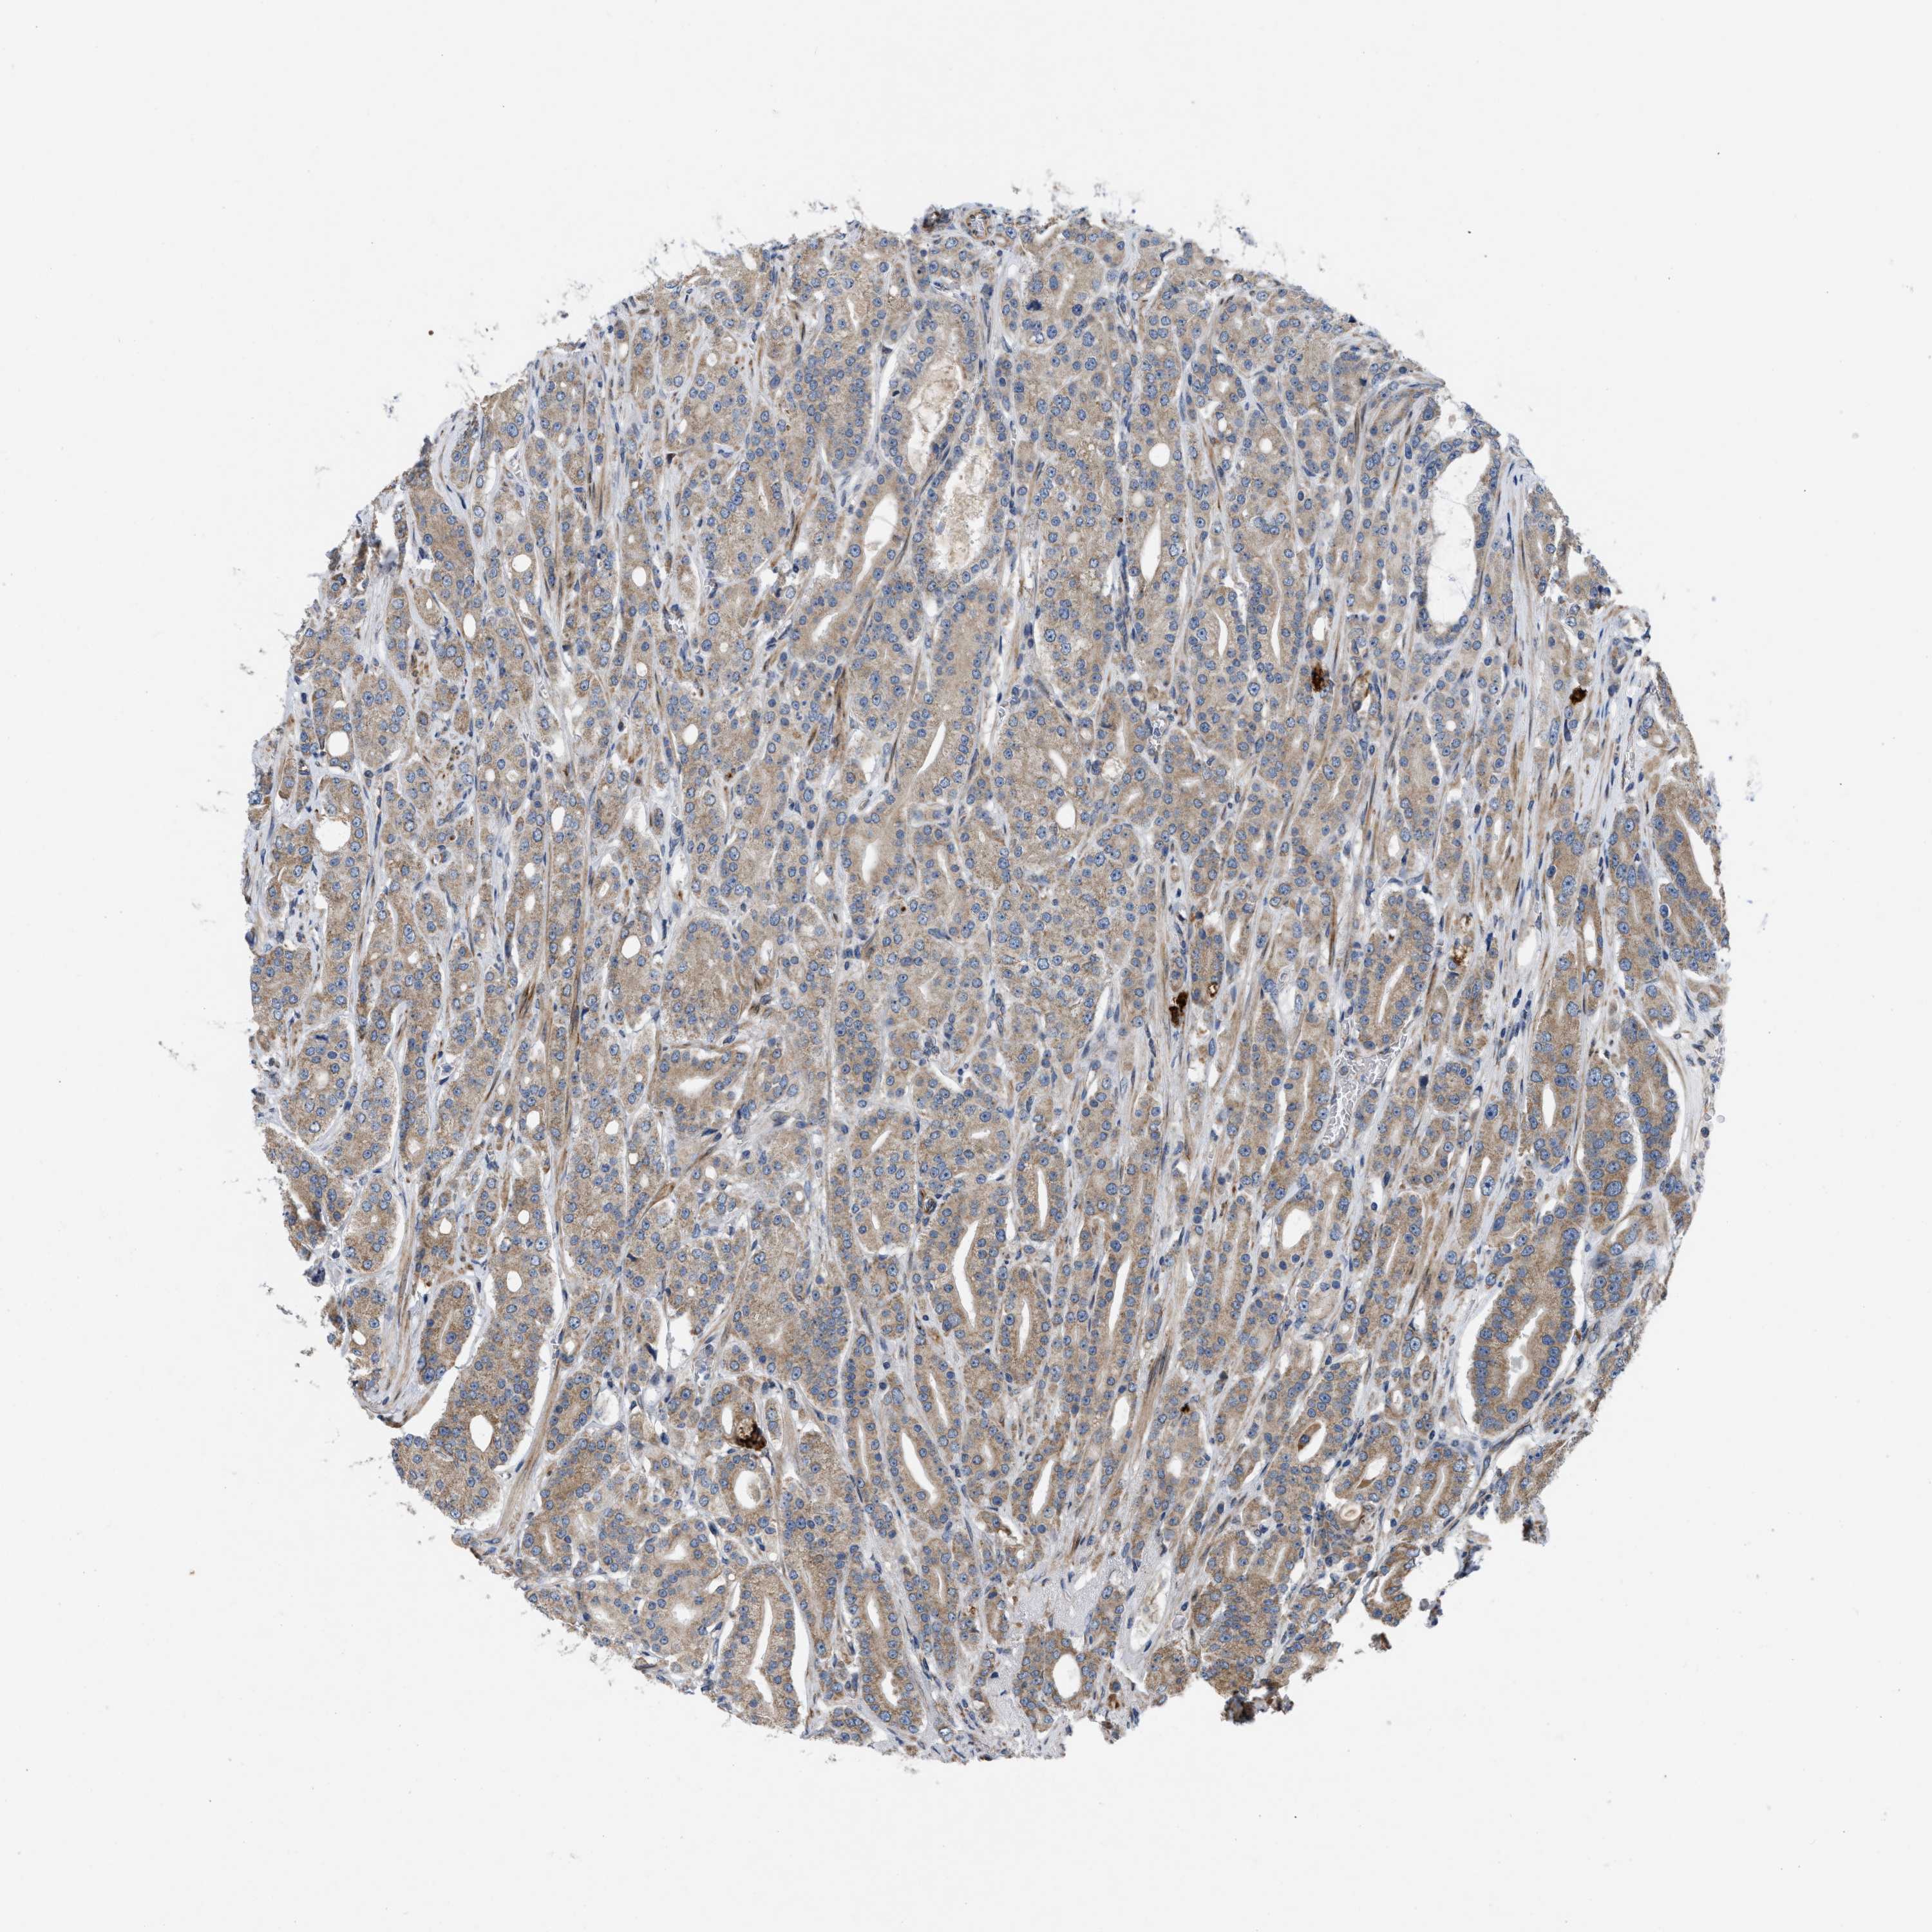

PROSTATE CANCER - Protein expressioni

A mouse-over function shows sample information and annotation data. Click on an image to view it in a full screen mode. Samples can be filtered based on level of antibody staining by selecting one or several of the following categories: high, medium, low and not detected. The assay and annotation is described here.

Note that samples used for immunohistochemistry by the Human Protein Atlas do not correspond to samples in the TCGA dataset.

Antibody stainingi

Antibody staining in the annotated cell types in the current human tissue is reported as not detected, low, medium, or high, based on conventional immunohistochemistry profiling in selected tissues. This score is based on the combination of the staining intensity and fraction of stained cells.

Each image is clickable and will lead to virtual microscopy that enables deeper exploration of all samples and also displays staining intensity scores, fraction scores and subcellular localization as well as patient and tissue information for each sample.

Antibody HPA019460

Staining

High

Medium

Low

Not detected

Intensity

Strong

Moderate

Weak

Negative

Quantity

>75%

75%-25%

<25%

None

Location

Nuclear

Cytoplasmic/membranous

Cytoplasmic/membranous,nuclear

Adenocarcinoma, High grade

Adenocarcinoma, Low grade